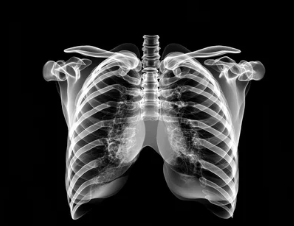

폐기흉(기흉, Pneumothorax)은 폐에 공기 주머니(기낭)가 터지거나 손상되면서 공기가 흉강(가슴막)으로 새어나와 폐가 수축하는 질환이다.

1. 폐기흉의 주요 증상 – 호흡 곤란 & 흉통

✔ 갑작스러운 가슴 통증 – 찌르는 듯한 통증, 한쪽 가슴에서 발생

✔ 숨 쉴 때 통증 증가 – 깊게 숨을 들이마시면 통증 악화

✔ 호흡 곤란 – 숨을 쉬기가 어려워지고 가슴이 답답함

✔ 기침 – 마른 기침이 자주 발생할 수 있음

✔ 피부색 변화 – 심한 경우 청색증(입술, 손톱이 푸르게 변함)

✔ 빠른 심장 박동(빈맥) – 심한 경우 쇼크 증상 동반 가능

📌 즉, 폐기흉의 주요 증상은 갑작스러운 가슴 통증, 호흡 곤란, 마른 기침, 빠른 심장 박동 등으로 나타날 수 있다.